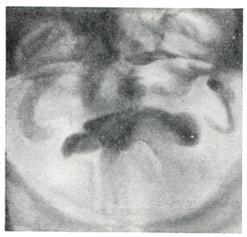

Эндоскопические методы исследования — цистоскопию, уретроскопию (см.) — следует проводить только при гематурии, подозрении на опухоль мочевого пузыря или для дифференциальной диагностики в неясных случаях. Уретроскопия показана в ранней стадии заболевания и не у пожилых, больных. При цистоскопии выявляются выбухания переходной складки в виде занавески (рис. 9), определяется средняя доля в виде барьера, уточняется наличие камней и сопутствующих заболеваний — цистита, язвы, папилломы. Во II и III стадиях заболевания цистоскопия затруднительна, может быть причиной развития инфекции, возникновения простатита и эпидидимита. Поэтому в последние годы большинство урологов предпочитает проводить цистоскопию в операционной перед операцией.